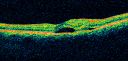

Serous Macular Detachment Left Eye - Possible Hypertensive Choroidopathy v. Central Serous Retinopathy683 views59-year-old woman decreasing vision in the left eye for about two days. She sees a spot in front of her vision. It is a yellow spot which is just straight ahead and moves with her eye. She does have high blood pressure. She checks her blood pressure at home, and even at home her blood pressure runs very high, with the systolic running around 200 and the diastolic around 100, although occasionally it does return to the normal range.

VISUAL ACUITY: Vision OD is 20/60, OS is 20/30Nov 30, 2010